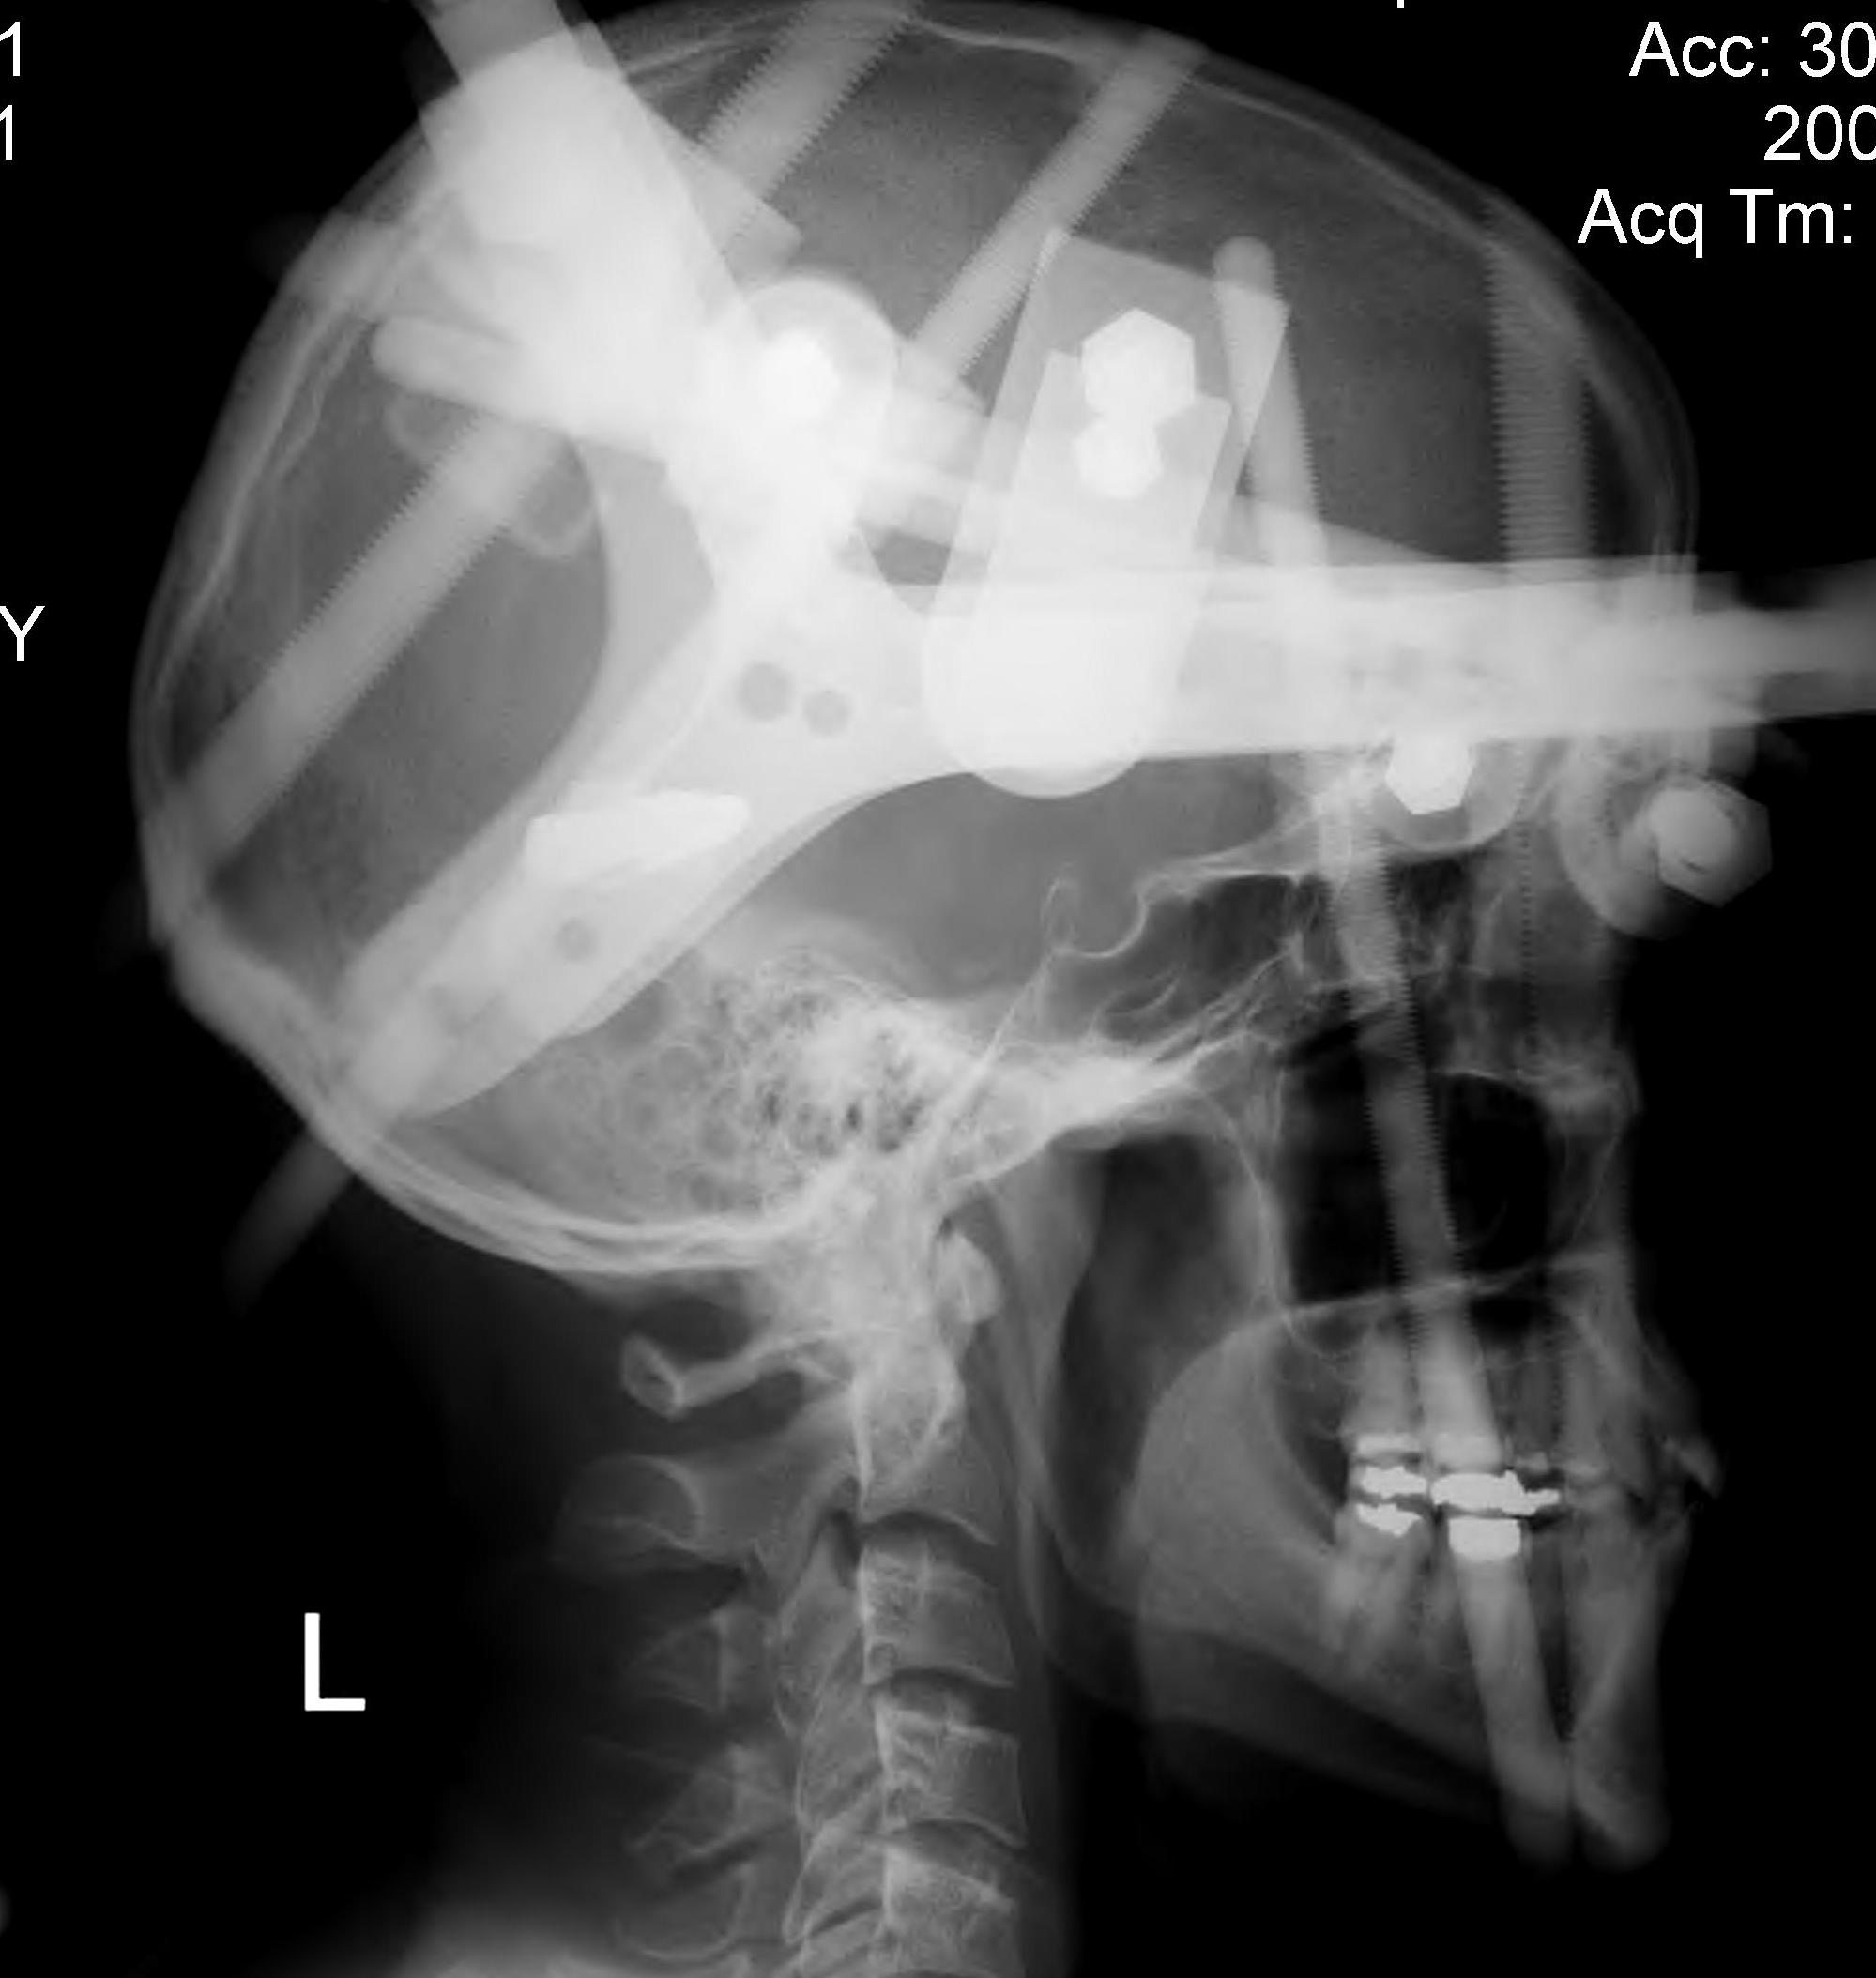

Jefferson HTB Xray

Post reduction halo xray